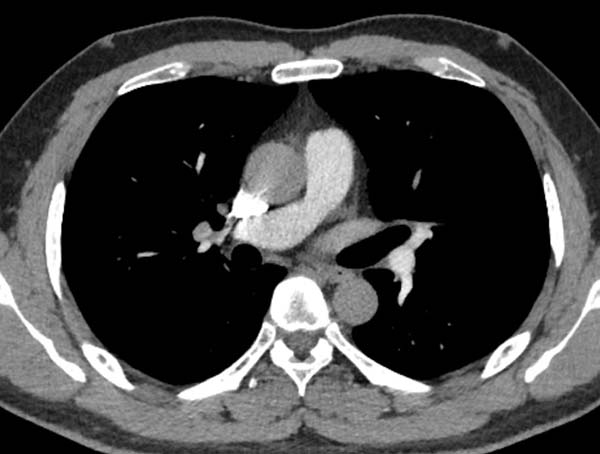

右锁骨下堵塞导致肺动脉充盈欠佳